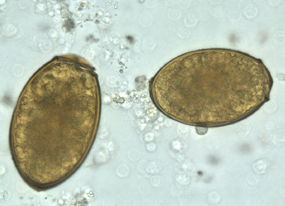

Schistosoma japonicum ova

Clonorchis sinensis ova

Clonorchis sinensis ova